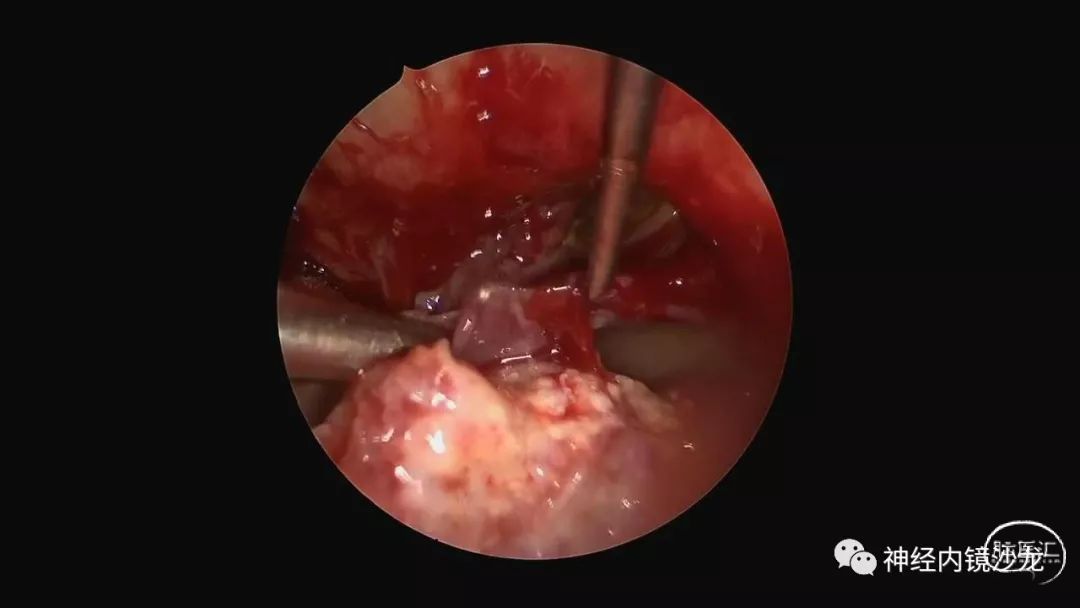

精彩图表

从事神经外科十余年,擅长神经外科肿瘤诊治,尤其是神经内镜微创手术治疗垂体瘤、颅咽管瘤、脑膜瘤等颅底肿瘤